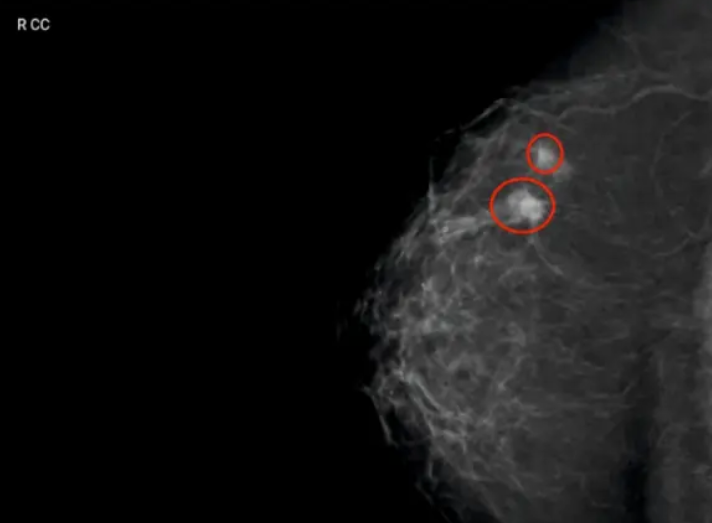

Снимки, получаемые с помощью искусственного интеллекта DIAR-MAMMO

Программное обеспечение использует интеллектуальные алгоритмы нейронных сетей и эффективный приемник для анализа получаемых геометрических данных о размере, плотности и оптимальной компрессии молочной железы, благодаря чему полученные изображения позволяют увидеть мельчайшие очаги поражения ткани молочной железы.

Обрабатывает геометрические данные и использует алгоритмы нейронных сетей для раннего выявления рака, кальцинатов, опухолей и воспалительных процессов. Кроме того, оно способно обнаруживать кистозные образования